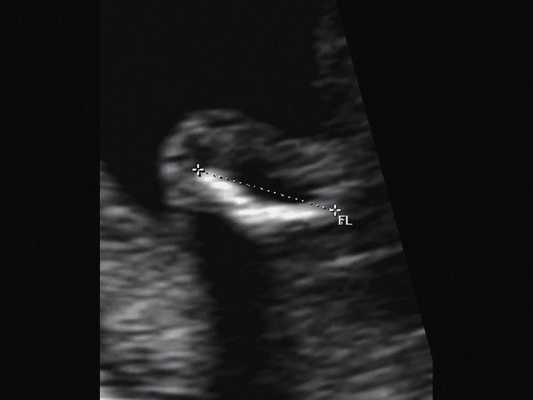

в) Изогнутая и укороченная бедренная кость.

г) Изогнутая и укороченная бедренная кость.

| Набл. 1. 24,3 нед. | БПР - 25,3 нед. ОГ - 24,6 нед. Аномально повышенная бороздчатость и выпуклость извилин нижнемедиальной поверхности височных долей (рис. 1а). | Торакоабдоминальное соотношение - 66,7% (рис. 1б) Длина ребра - среднее для 16 нед. | Бедренная кость 19,6 мм (47,8% от должной), изогнута ("телефонная трубка") (рис. 1в). Остальные кости - среднее для 15 нед. | Уплощенные тела поясничных позвонков. |

| Набл. 2. 20,3 нед. | БПР - 21,5 нед. ОГ - 20,3 нед. Уплощенный затылок. Выпуклые темпоральные бугры (рис. 2а). Аномально повышенная бороздчатость и выпуклость извилин нижнемедиальной поверхности височных долей (рис. 2б). | Торакоабдоминальное соотношение - 63,3% (рис. 2в) Окружность груди - среднее для 18 нед. Длина ребра - среднее для 15 нед. | Бедренная кость 17,7% (61% от должной), изогнута ("телефонная трубка") (рис. 2г). Остальные кости - среднее для 13-14 нед. | Гипоплазия костей носа. |

| Набл. 3. 24 нед. | БПР - 30 нед. ОГ - 27,2 нед. Уплощенный затылок. Выпуклые темпоральные бугры (рис. 3а). Аномально повышенная бороздчатость и выпуклость извилин нижнемедиальной поверхности височных долей (рис. 3б). | Торакоабдоминальное соотношение - 56,6% (рис. 3в) Окружность груди - среднее для 20 нед. Сердце/грудь (см 2 ) - индекс 0,6. | Бедренная кость 23,1 мм (57% от должной), изогнута ("телефонная трубка") (рис. 3г) Остальные кости - 50% для 15-16 нед. Нормальная установка пальцев кисти (рис. 3д). | Многоводие. |

| Набл. 4. 26,5 нед? | БПР - 22,6 нед. ОГ - 22,6 нед. Форма - трилистник (рис. 4а). Боковые желудочки - 22 мм, высокий лоб, расширенный родничок, сагиттальный шов (рис. 4б). | Торакоабдоминальное соотношение - 65,7% (рис. 4в). Окружность груди - среднее для 23 нед. Колоколообразная форма. | ДБ - 23 мм (51% от должной). Остальные кости - 50% для 15-17 нед. Нормальная установка пальцев кисти (рис. 4б). | Уплощенные тела поясничных позвонков (рис. 4г). |

В наблюдениях 1-3 наличие изогнутой бедренной кости (по типу "телефонной трубки") (рис. 1в, 2г, 3г) позволяло предположить наличие ТД I типа. Целе направ ленное исследование головного мозга этих плодов в дополнение к описанным скелетным признакам показало и картину ДВД. Была выявлена аномально повышенная бороздчатость и выпуклость извилин нижнемедиальной поверхности височных долей у плодов в наблюдениях 1-3 (рис. 1а, 2б, 3б). Это позволило установить диагноз ТД I типа.

Наиболее важным, с точки зрения A.M. Bircher и соавт. [16], является необходимость дифференцировки ТД с ахондроплазией, так как последняя является частой и совместимой с жизнью скелетной дисплазией. При этом наиболее эффективным дифференциальным признаком предлагается степень укорочения бедренной кости: невыраженное укорочение (ДБ составляет до 80% от должной) характерно для ахондроплазии, тогда как при ТД укорочение выраженное (ДБ составляет 30-60%). В наших наблюдениях укорочение ДБ составляло 47-61% от должной. В работе A. Khalil и соавт. [17] показано увеличение диафизарно-метафизарного угла (более 130°) бедренной кости при ахондроплазии. С нашей точки зрения, в дифференциальной диагностике ТД с гомозиготной формой ахондроплазии решающую роль может играть семейный анамнез, а с гетерозигототной - наличие узкой грудной клетки. Кроме того, как видно по нашим наблюдениям, при ТД определяется правильная установка пальцев кисти (рис. 3д, 4б) в отличие от ахондроплазии, при которой определяется установка пальцев в виде "трезубца".